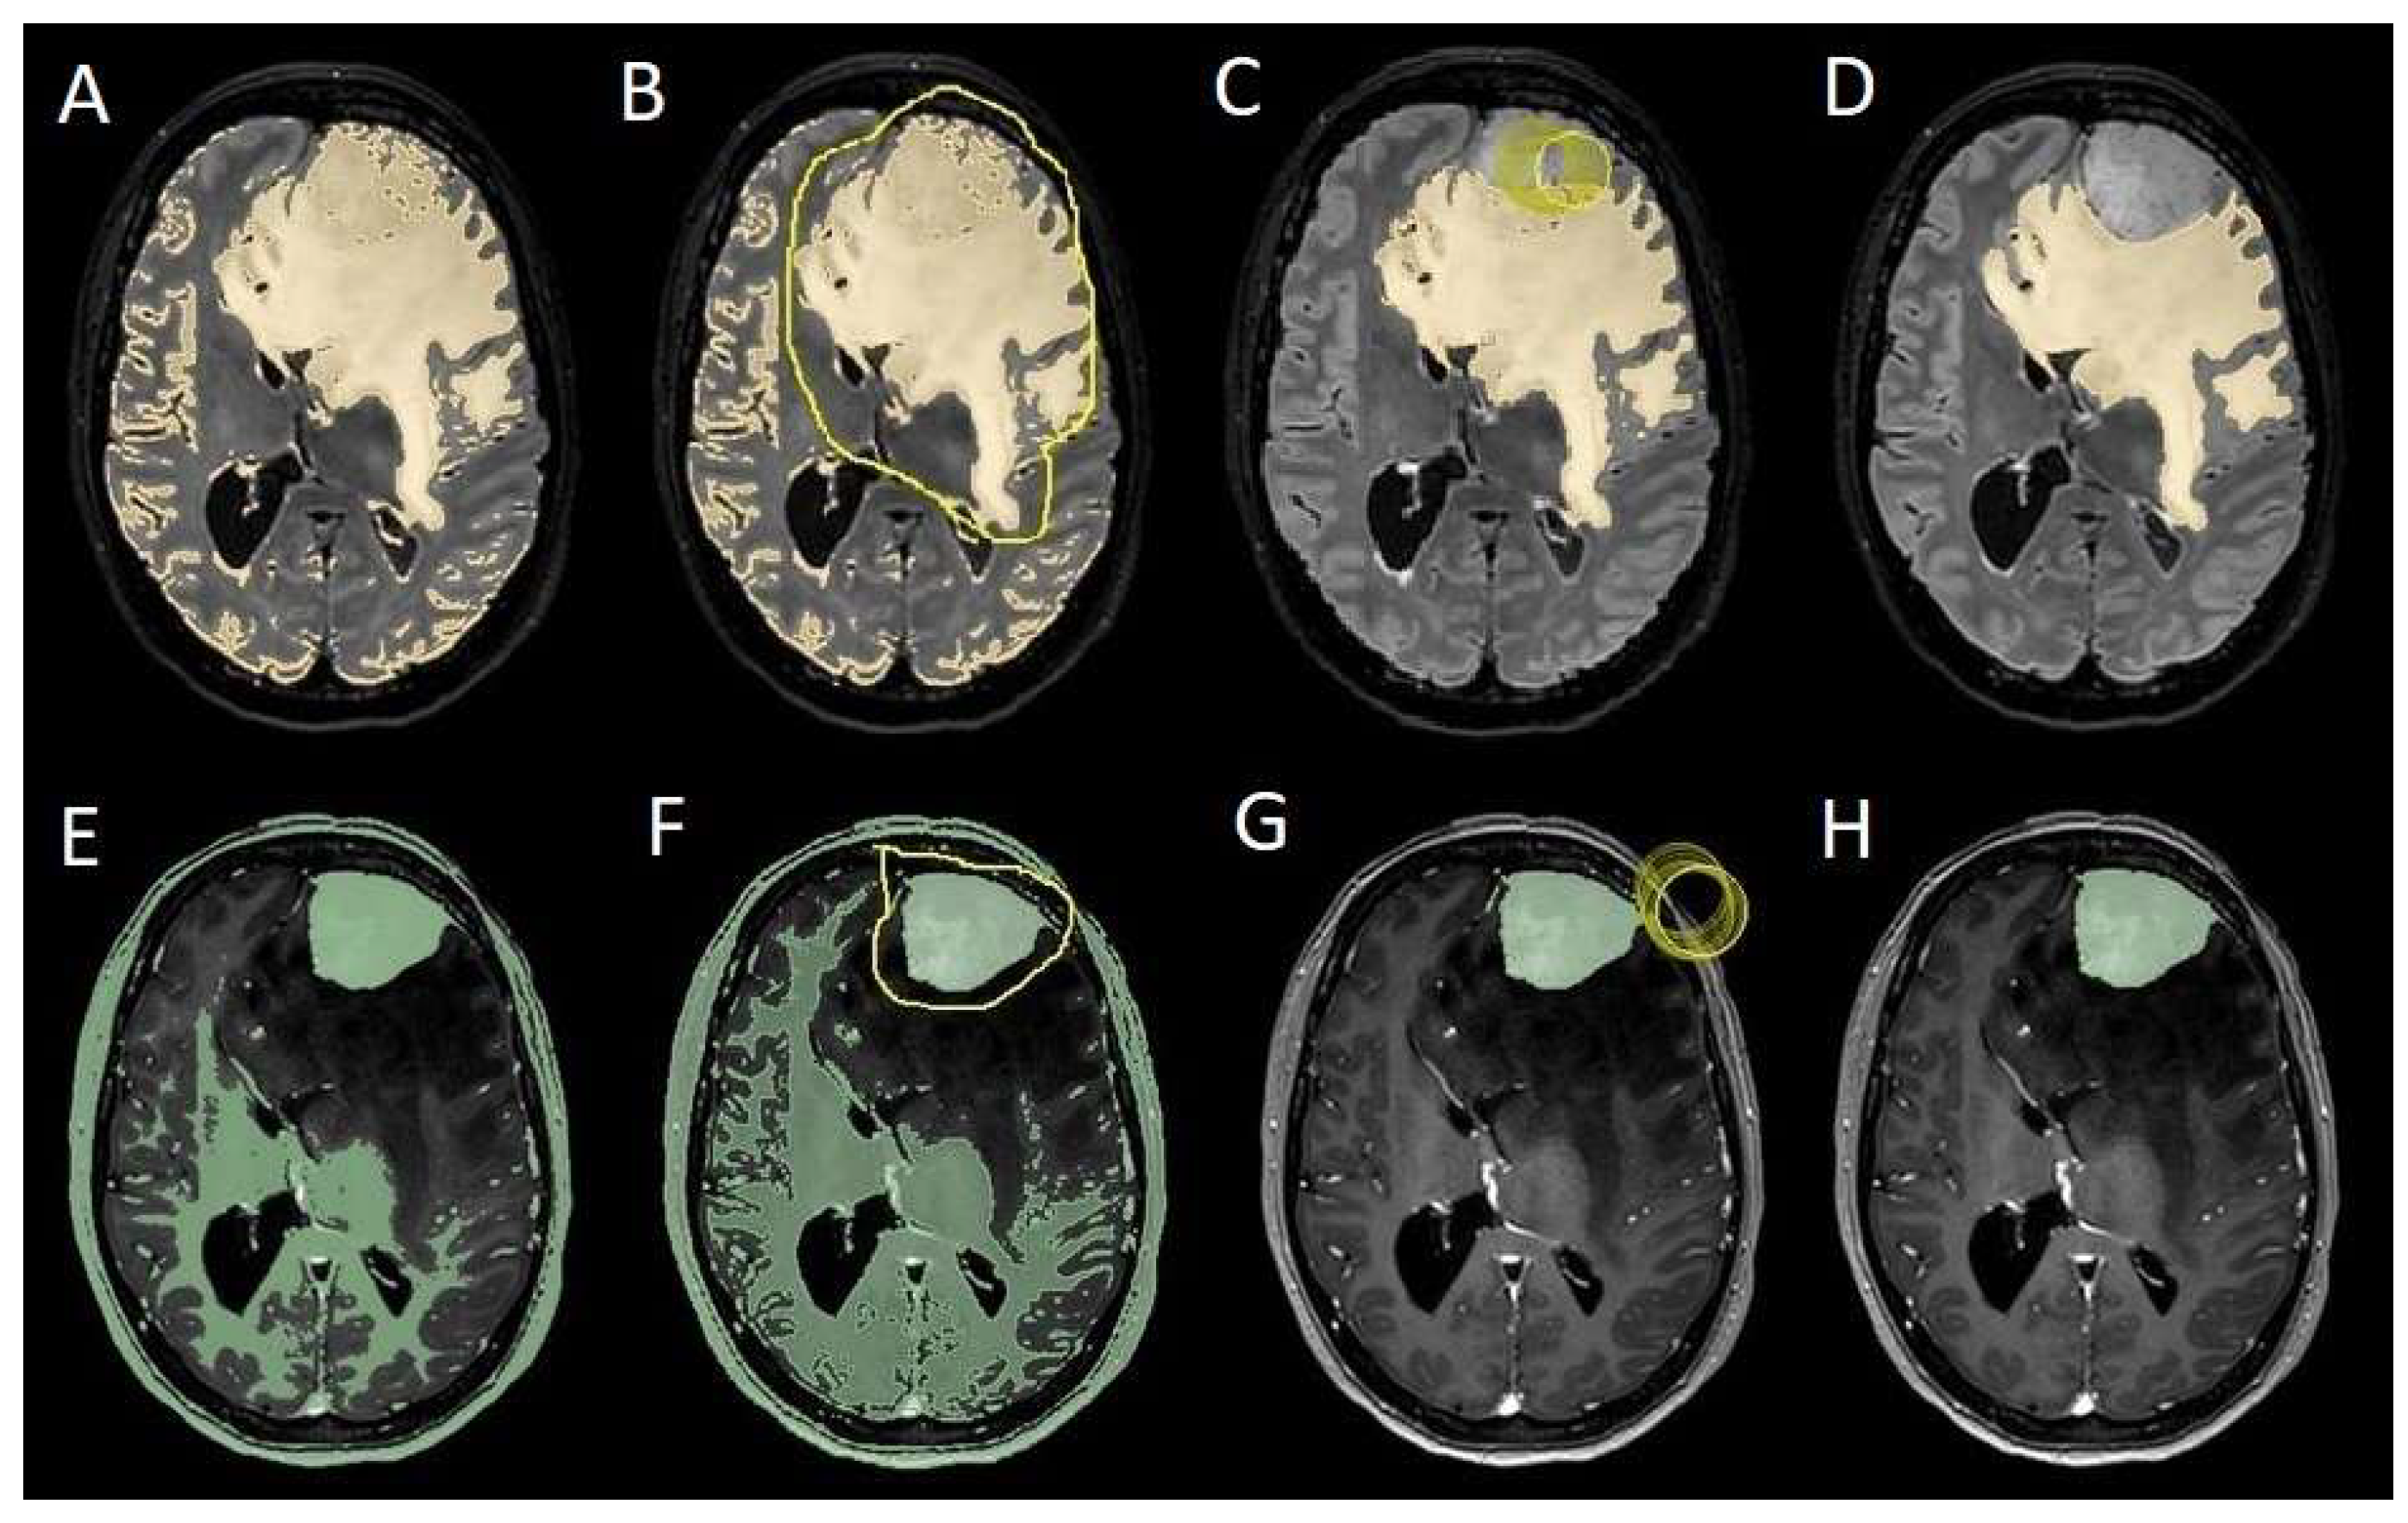

The patients underwent magnetic resonance imaging (MRI) at our center using a 1.5T or 3T Tesla MRI machine (Ingenia 3T, Philips Medical Systems, Best, The Netherlands) with the standard oncological protocol [14]. Specifically for analysis, the sequences collected were T1-weighted with contrast enhancement to estimate tumor volume and conformation and FLAIR (fluid-attenuated inversion recovery) to quantify PE (Figure 1). We manage the preoperative imaging in a DICOM (digital imaging and communications in medicine) format. The images from the T1-weighted sequences with contrast enhancement and FLAIR sequences in the DICOM format were processed through the Slicer website [15]. Tumor and PE segmentation was performed using a voxel-based analysis that integrated automated and manual methods (Figure 2).

The process begins with an automatic thresholding technique to identify initial regions of interest based on intensity values (Figure 2A,E). This is followed by manual refinement to enhance accuracy and delineate precise boundaries (Figure 2B,C,F,G). The final segmentation provides volumetric measurements for both the tumor and the PE, aiding in quantitative analysis (Figure 3). The included patients’ pre- and post-treatment clinical data were retrospectively extracted from our center’s computerized database. Collected data included demographic information, preoperative clinical details (presence or absence of epilepsy, onset symptoms, ASM therapy and number of ASMs taken, and radiological characteristics of the meningioma), and postoperative data (Engel class [16], persistence or discontinuation of ASMs, ASM discontinuation timing, and possible postoperative functional deficits). A single examiner conducted data collection to minimize subjective variability in assessments. Surgical procedures were performed using a transcranial approach under general anesthesia. We excluded cases of surgical resection performed via an endoscopic endonasal approach. Cases of postoperative death (within one year after surgery) were excluded. The extent of resection (EOR) was determined based on the postoperative MRI (usually one month after surgery) and classified according to the Simpson grading system [17]. This study included cases of complete macroscopic meningioma resection (Simpson I, II, and III). Cases with residual tumor persistence or recurrence after surgery (Simpson IV and V) were excluded (Figure 4).

Figure 2. Example of segmentation process with the Slices website. (A,E) Automatic thresholding technique to identify initial regions of interest based on intensity values, respectively, for the PE on the FLAIR sequence and the meningioma on the T1-weighted-with-gadolinium sequence. (B,F) Partially automatic erasure of redundant signal with “erase outside” tool. (C,G) Definition of boundaries of edema and tumor through manual erasure. (D,H) Final segmented volumes. FLARI: fluid-attenuated inversion recovery; PE: peritumoral edema.

Figure 4. Segmentation process for PE < 1 cm3. (A,E) Automatic thresholding technique to identify initial regions of interest based on intensity values, respectively, for the PE and the meningioma. (B,F) Partially automatic erase of redundant signal with “erase outside” tool. (C) Precisely definition of boundaries of edema through manual erasure, cutting all around redundant signal. (G) Manual erasing boundaries for tumor volume. (D,H) Final segmented volumes. PE: peritumoral edema.